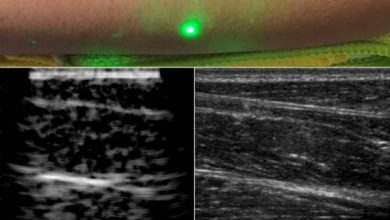

ليزر لأخذ صور داخل الجسم عن بعد

اكتشف باحثون في معهد ماساتشوستس للتقنية بديلا بالليزر في الموجات فوق الصوتية العادية، والذين أوضحوا في سبق صحفي، أن آليتهم…